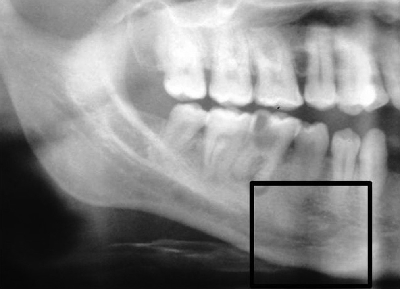

Can dental implants be done in one day?

Dental Procedures in One Day are unique because teeth, teeth that are fully functioning can be applied on the same day when you receive a dental implant. See the article : Dental Implant Procedure Steps. The temporary teeth remain in place until your custom, permanent teeth are ready to be placed.